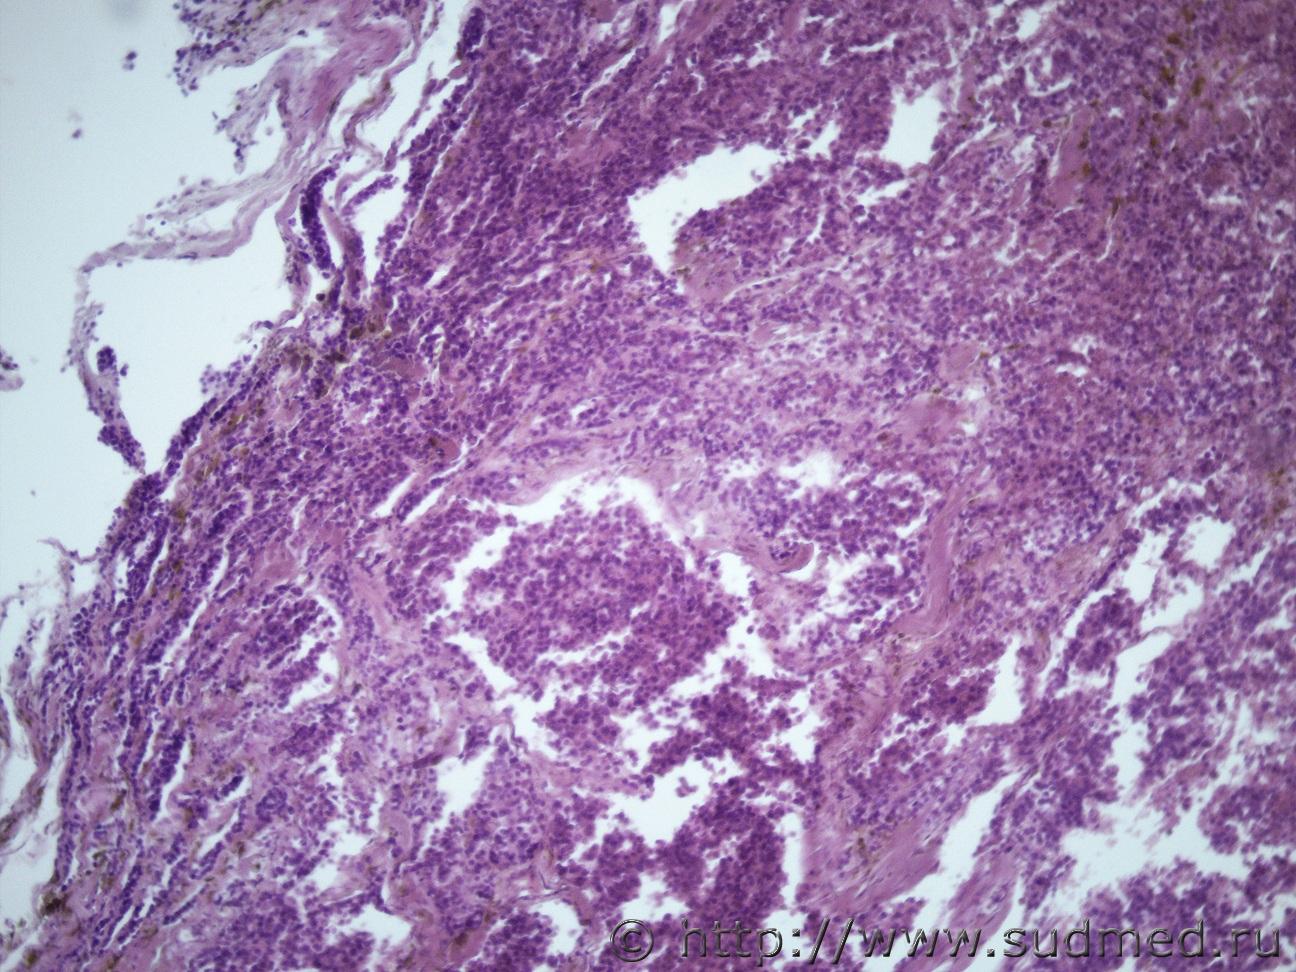

Ув. коллеги помогите определиться с раком. Муж 60 лет. Новообразование предстательной железы с метастазами в легкие, печень, диафрагмуСудебная медицина - Прикрепленное изображение Судебная медицина - Прикрепленное изображениеСудебная медицина - Прикрепленное изображениеСудебная медицина - Прикрепленное изображениеСудебная медицина - Прикрепленное изображение

Поставил бы криброзную ад-карциному.

В данном случае можно поставить аденокарциному. Если на первых фото ткань простаты, то можно сказать, что опухоль с высоким индексом Глисона, видны солидные пласты опухолевых клеток, хотя кое-где все же прослеживаются железистые структуры. Более прицельные снимки бы глянуть, на большем увеличении.

Ацинарная аденокарцинома.

криброзную

Есть и эти структуры.

Да первые это простата. Вот еще снимки